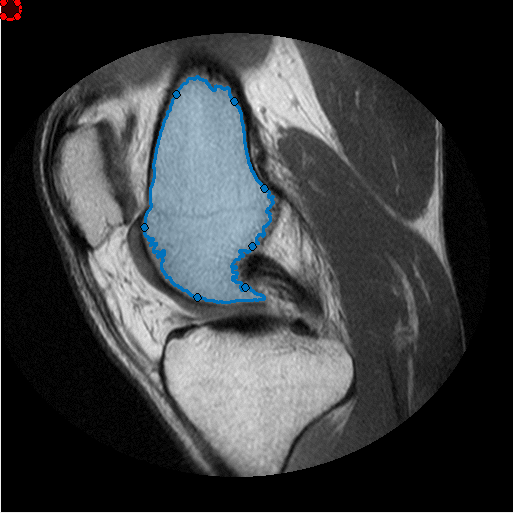

Создайте ROI От руки, который следует за формой маски сегментации. Для получения дополнительной информации об этом процессе смотрите Использование ROI От руки, чтобы Совершенствовать Маски Сегментации.

Сегментируйте изображение MRI и выберите две самых больших области рисунка маски.

segmentedLabels = imsegkmeans(im,3); boneMask = segmentedLabels==2; boneMask = bwareafilt(boneMask, 1);

Получите координаты контуров двух сегментированных областей.

blocations = bwboundaries(boneMask,'noholes');

Создайте ROI от руки в сегментированной маске.

hf = drawfreehand('Position', pos);